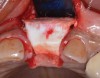

Occasionally, when a fractured implant is removed via a trephine drill, a wider implant can be placed that will still be within the osseous envelope and respectful of physiologic and esthetic guidelines (Figure 6 through Figure 10). After explantation of an implant with a 3.6-mm diameter body that tapered to 2.5 mm apically, a coronally tapered 4.2-mm diameter implant with a 2.5-mm apical diameter (Astra Tech, Dentsply Sirona) was placed with adequate implant stability. The facial bone lost secondary to the fracture was augmented simultaneously with immediate implant replacement.

(6.) A 3.6-mm diameter implant was removed with a 4.0-mm diameter trephine drill. The apical portion of the implant was luxated carefully to preserve as much bone as possible.

Figure 6

(7.) Because apical and lateral bone volume was preserved with use of an ultrathin trephine, a wider diameter, 4.2-mm implant was placed at the time of implant removal. Bone augmentation was performed, and submerged healing was selected.

Figure 7